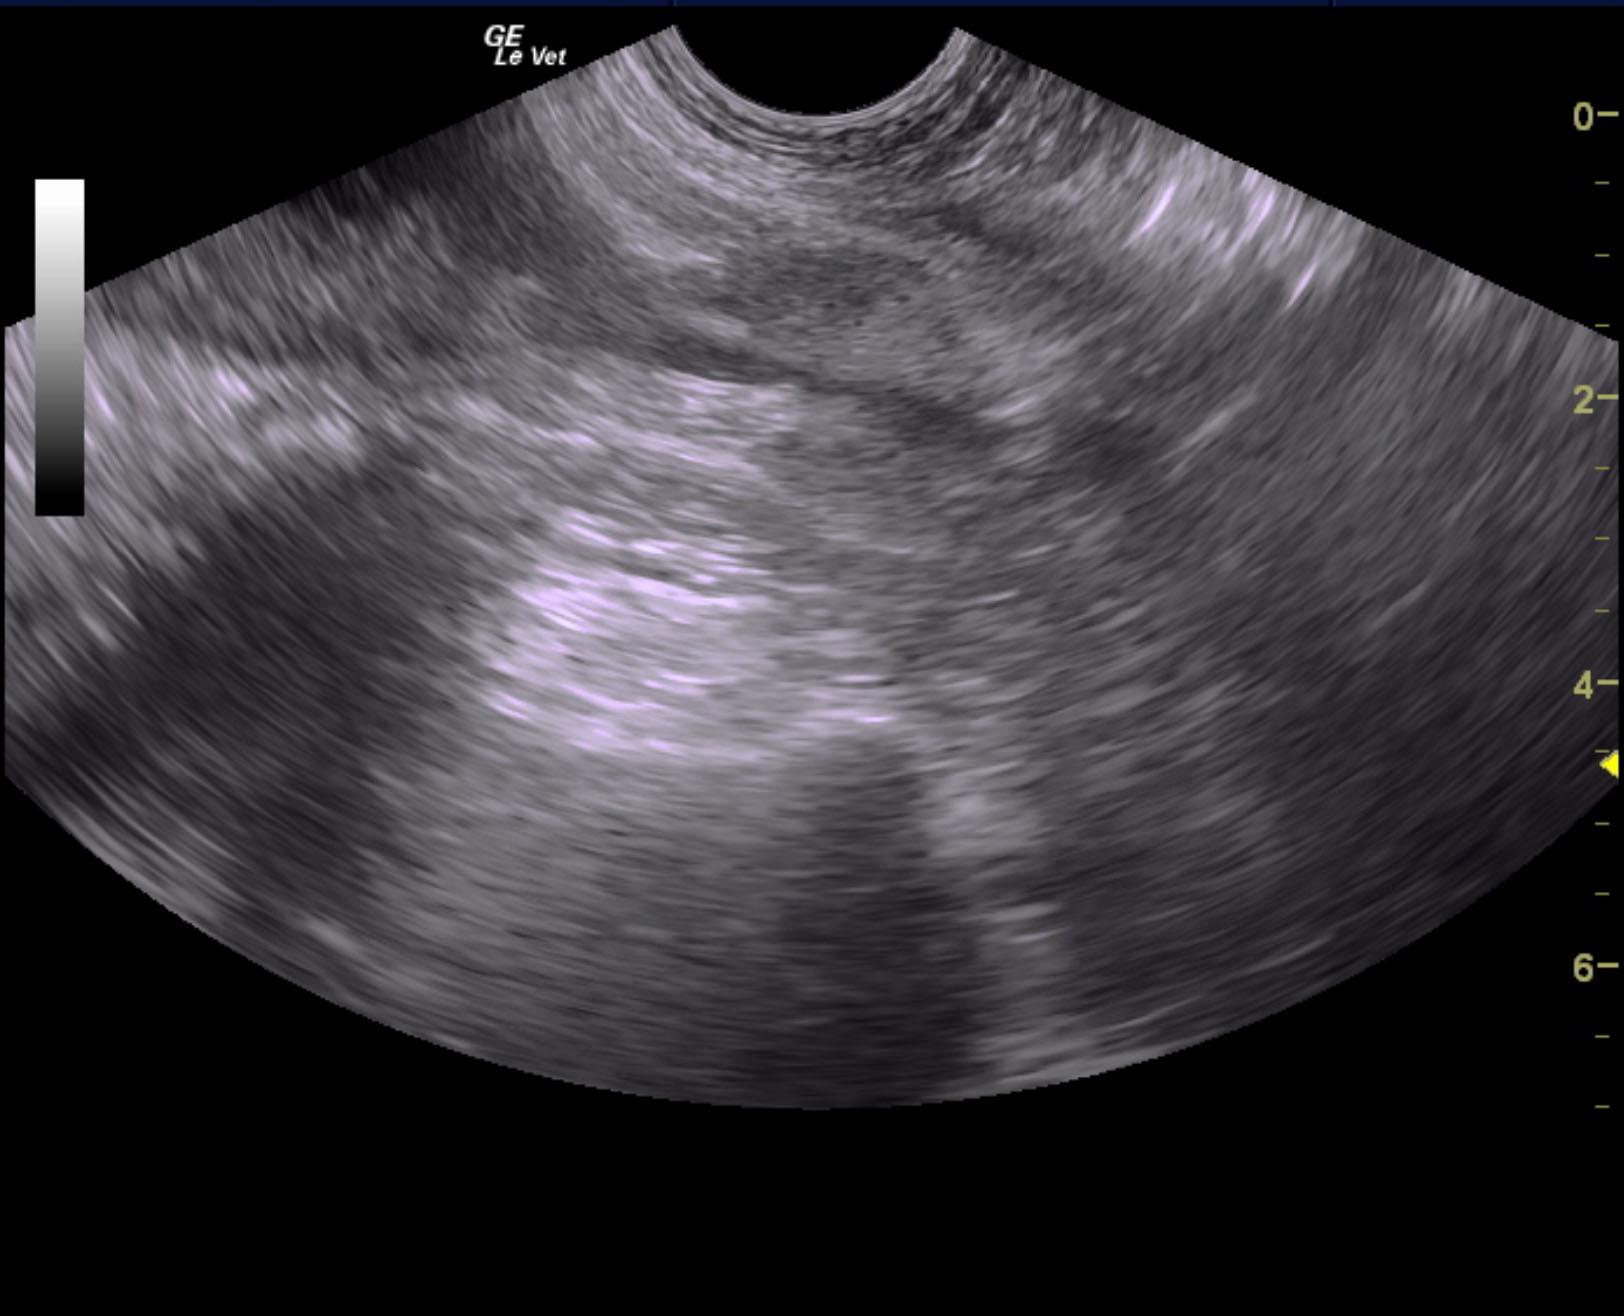

A 5-years-old male neutered Shih Tzu was presented for evaluation of urethral obstruction that had been managed with catheterization. Urinalysis showed SG of 1.008 and proteinuria. Abnormalities on CBC and serum biochemistry were neutrophilia and monocytosis, elevated phosphorus, and azotemia; the latter had improved after being catheterized.